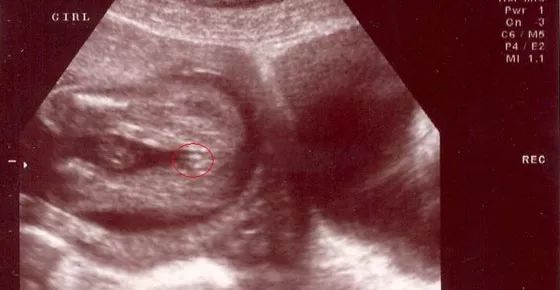

女宝宝四维彩超图

三条白线是明显的女宝特征,如果没有看到明显的三条白线,就看两腿之间有没有突出的东东,且中间有小凹槽的,就是女宝